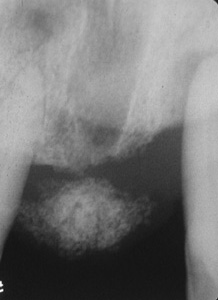

Radiografía

de la lesión en la imagen anterior revela la formación de hueso, que no es

un hallazgo raro en este tipo de lesión.